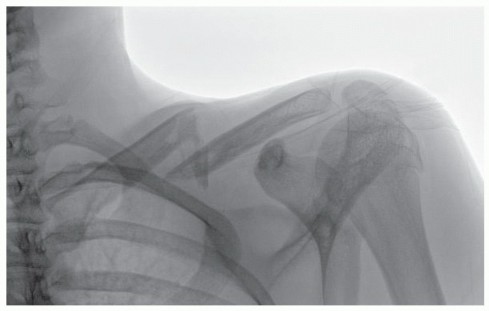

DEFINITION Brett D. Owens Joanna G. Branstetter Thomas P. Goss Intra-articular scapular fractures include fra…